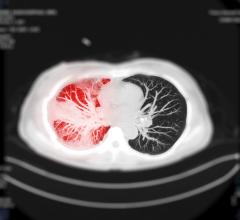

November 22, 2023 — Lung cancer is one of the world’s silent killers. By the time patients experience symptoms, the ...

November 1, 2023 — Annalise.ai, a global leader in the radiology imaging sector, announced the launch of Annalise Triage ...

September 20, 2023 — Medical imaging artificial intelligence (AI) company Annalise.ai has announced that the results ...